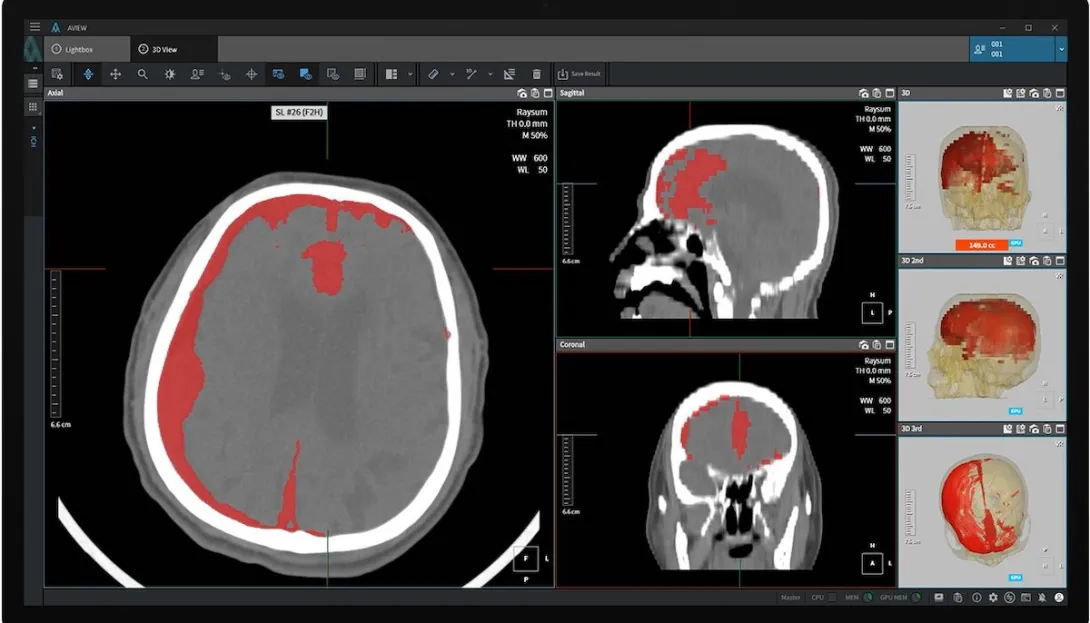

An AI-powered brain haemorrhage detection software by medtech company Coreline Soft is now listed as a non-insured medical device in South Korea following its approval from the Ministry of Food and Drug Safety.

The software product called AVIEW Neuro CAD automatically detects cerebral haemorrhages in brain CT scans and sorts them according to severity. It was recognised as an innovative medical device in South Korea last year.